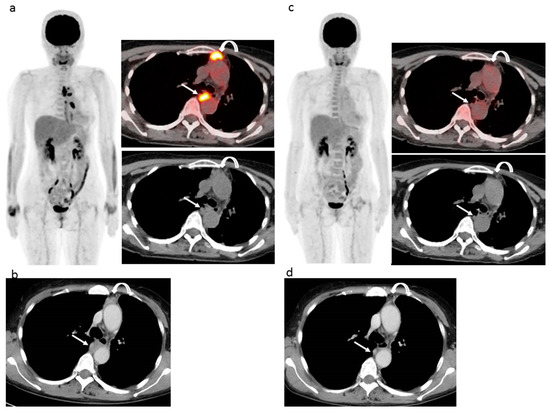

Figure 1.

61 year-old woman with left epithelioid malignant pleural mesothelioma who previously received neoadjuvant chemotherapy (pemetrexed + cisplatin), pleurectomy, and decortication surgery (pT3N1M0), then six cycles of chemotherapy (pemetrexed + cisplatin) after the operation, followed by 10 cycles of second-line therapy (irinotecan + gemcitabine) and then nivolumab as third-line chemotherapy. (a) Pre-nivolumab treatment FDG-PET/CT shows several areas of strong FDG uptake related to a pleural lesion (curved arrow) and mediastinal lymph nodal lesion (arrow). (b) Pre-nivolumab treatment contrast-enhanced CT shows mass-forming thickness of pleura lesion (curved arrow) and mediastinal lymph nodal lesion (arrow). (c) During-treatment FDG-PET/CT after 13 cycles of nivolumab shows FDG uptake disappearance in both pleural (curved arrow) and nodal (arrow) lesions. (d) During-treatment contrast-enhanced CT after 13 cycles of nivolumab shows remarkable improvements of both pleural (curved arrow) and nodal (arrow) lesions. EORTC, PERCIST, and imPERCIST indicated CMR. Interpretation of combined modified RECIST and RECIST 1.1 indicated a classification of PR, with the sum pleural lesion size decreasing by 45.5% and the sum mediastinal node size decreasing by 78.3%. The patient continued with 29 more cycles of nivolumab and was alive without progression at 15.1 months after nivolumab initiation.